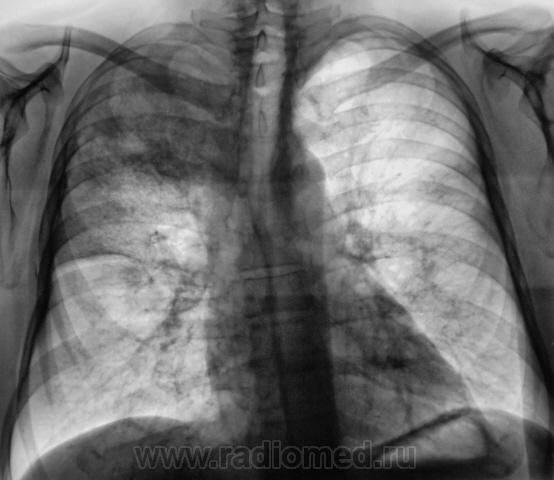

Пациент направлен на рентгенографию ОГК с подозрением на пневмонию.

Валентин Львович и так все знает, что делать, поэтому советовать ничего не буду, только скажу, что пока я за пневмонию.Инфильтрация больше пневмоническую напоминает,междолевая плевра отреагировала,

В клинике тоже,думаю, проявления неспецифического процесса преобладают.

По прямой рентгенограмме в больших сомнениях пребывал - сомнения по поводу абсцедирования...

Клиника манифестная, на крупозную тянет, "мужик" здоровенный, вчера температура до 40.